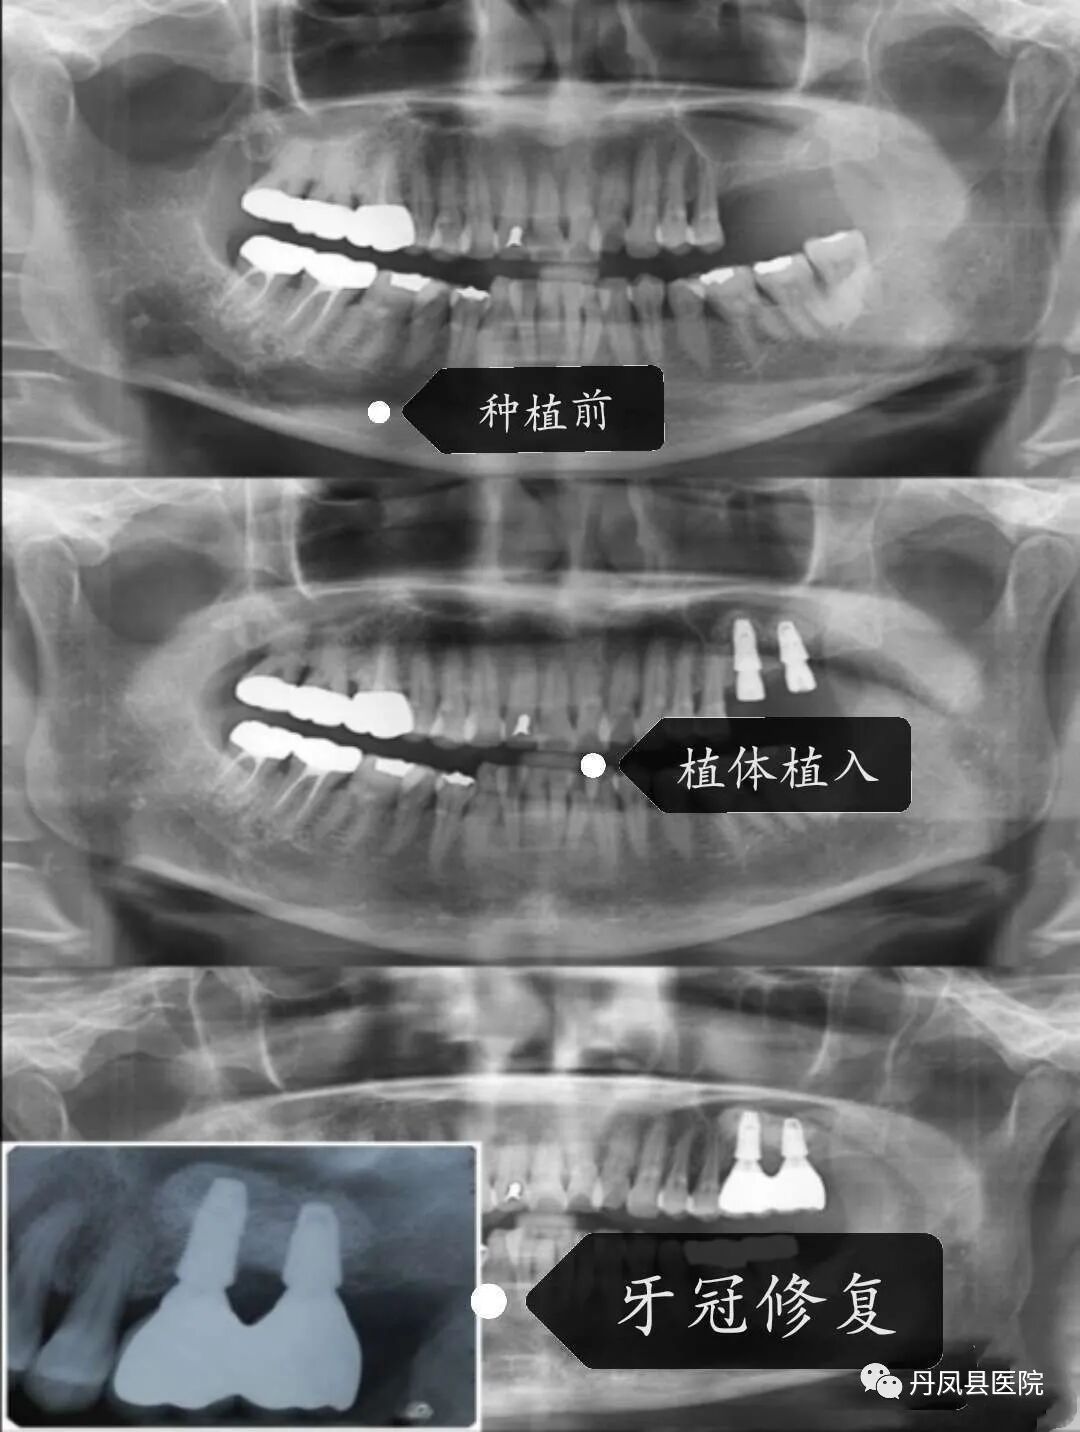

①种植牙:种植牙---人类的第三幅牙。种植牙在不损伤相邻健康牙的情况下,并且以超高的咀嚼效率及逼真的美观效果恢复了牙体缺失的情况。种植牙使用寿命长、异物感小,人工牙根的刺激抑制了由于牙根缺失造成的牙槽骨萎缩现象。我科已开展种植牙业务,并拥有专业的医疗团队、先进的种植设备、熟悉的种植技术和无菌的手术环境,这些条件无一不为种植术的成功添砖加瓦。![]()